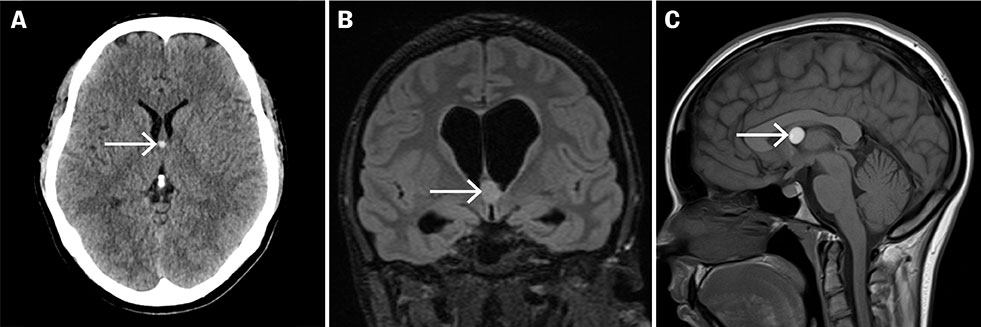

CT av hjernen med standardsekvenser uten kontrast viser kolloidcyster som en velavgrenset, rundlig, hyperdens lesjon i midtlinjen i tett kontakt med de interventrikulære foramina (figur 1a) (7). Dersom kolloidcystene blokkerer sideventriklene vil man kunne se biventrikulær hydrocefalus og utvisket kortikalt relieff som uttrykk for økt intrakranialt trykk (figur 1b). På MR-undersøkelse av hjernen vil kolloidcyster i to tredjedeler av tilfellene ha et hyperintenst T1-signal, mens T2-signalet ofte er isointenst med omliggende hjerneparenkym (6). Kolloidcyster som er i ferd med å øke i størrelse, har høyere vanninnhold, og i så fall vil de være hypointense på T1-vektede serier og hyperintense på T2-vektede serier (8). Slike funn kan vektlegges når man vurderer videre observasjon eller kirurgi for pasienter med få eller ingen symptomer.

I nevnte artikkel (5) ble det foreslått en risikoskår for å avgjøre symptomatisk status og dermed bidra til å klargjøre behov for behandling. Risikoskåren beregnes basert på følgende kriterier: alder < 65 år, hodepine, aksial diameter ≥ 7 mm, MR caput FLAIR-hyperintensitet og risikosone (tabell 1). Risiko ved kolloidcyster knyttes til de anatomiske forholdene i tredje ventrikkel og om det er sannsynlig at kolloidcyster kan blokkere interventrikulær foramen eller akvedukten. For å bedømme denne risikoen benyttes sagittale MR-sekvenser. Dersom kolloidcystene er lokalisert i fremre eller bakre del av tredje ventrikkel, svarer dette til økt risiko og således ett poeng (figur 1c). Denne risikoskåren er validert i en senere studie (9) og er i tråd med en annen retrospektiv studie (10). Ved en risikoskår ≥ 4 poeng foreligger høy risiko og assosiasjon med obstruktiv hydrocefalus, og kirurgi anbefales. Dersom risikoskåren er ≤ 2, foreligger lav risiko. Man kan da avvente kirurgi og heller gjennomføre klinisk og radiologisk kontroll. En innvending mot risikoskåren er at den ikke vektlegger om det foreligger billedmessig hydrocefalus.